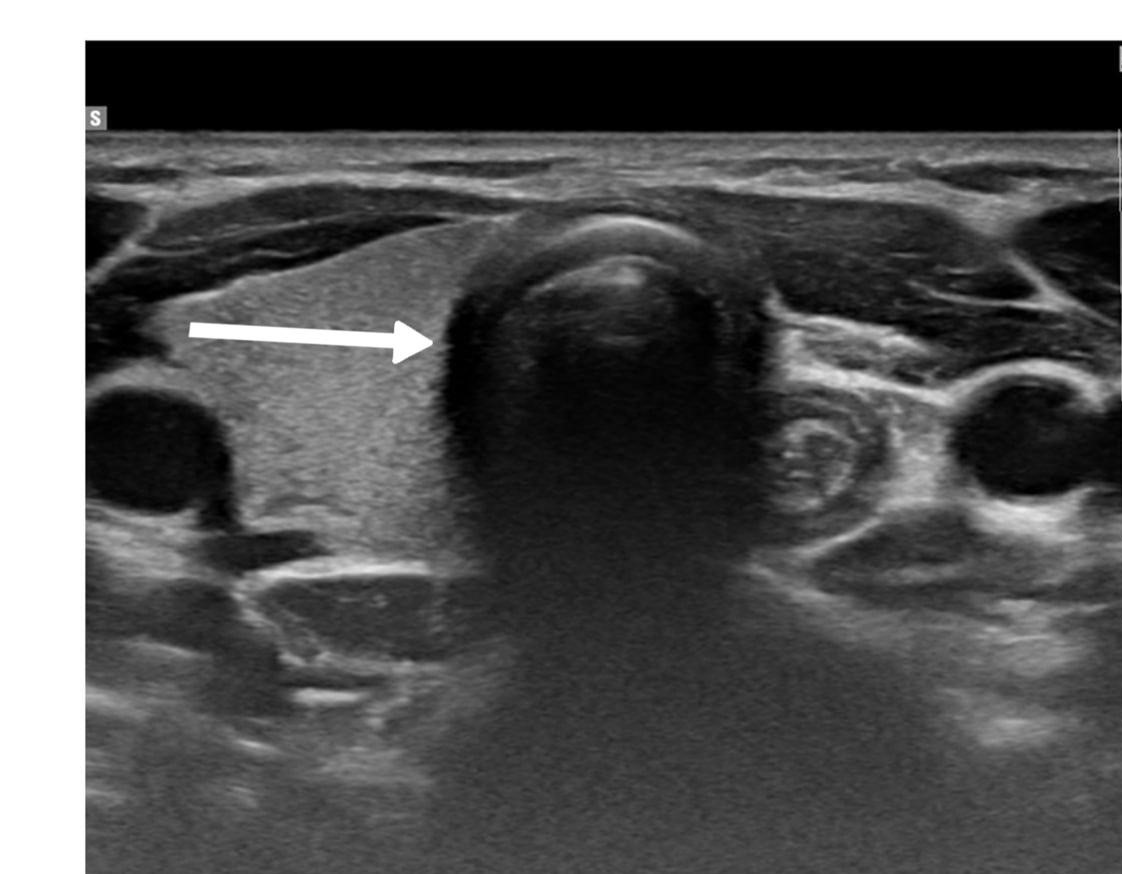

The diagnostic evaluation of most thyroid nodules typically begins with U/S, followed by fine needle aspiration (FNA). The U/S findings suggestive of HTT are well-defined, solitary, oval or round, solid hypoechoic nodules, usually without microcalcifications and displaying peri or intra-nodular vascularity. However, these features are not specific to HTT and may also occur in other thyroid lesions [7]. Recognizing the variability in U/S findings is crucial, as some studies reported an absence of malignant features. In contrast, Choi et al. found that 29% of HTT cases displayed malignant features on U/S [5,11]. In the present study, five cases were classified as mildly suspicious for malignancy, and three were considered moderately suspicious for malignancy according to the thyroid imaging reporting and data system (TI-RADS). Among the reviewed cases, malignancy was also suspected in four patients based on the U/S findings [2,3,7-10].

Thyroid function assessment revealed that the majority (7 cases ,63.6%) of patients were euthyroid (0.35-4.5µIU/mL), while two patients exhibited hyperthyroidism (<0.35 µIU/mL), and two of them had hypothyroidism (>4.5 µIU/mL). Ultrasound findings demonstrated left lobe and isthmus agenesis in eight cases (72.7%), while two cases (18.2%) exhibited isolated left lobe agenesis, and one patient exhibited isolated right lobe agenesis (9.1%) (Figures 1 and 2). The largest documented normal lobe measured 100 × 43 × 35 mm, whereas the smallest measured 15 × 6.9 × 7.9 mm. The follow-up period ranged from 4 to 48 months (Tables 1-3).